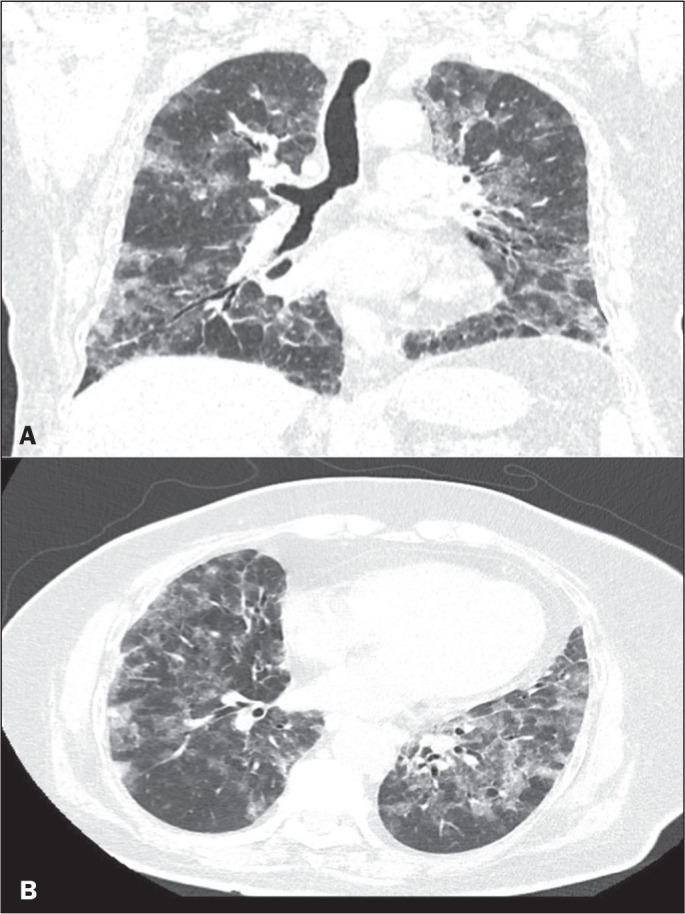

目的:评估2019冠状病毒(COVID-19)感染者典型CT扫描频率,并比较接种疫苗和未接种疫苗的人群。材料与方法:对2021年8月至2022年2月期间临床疑似COVID-19患者的病历进行回顾性研究。疫苗接种状态分为未接种/未接种(0或1剂)或已接种(2剂或更多剂)。在第一次胸部CT上所见的模式被定义为典型、非典型、不确定或正常,后三种模式被合并为非典型组。结果:二元logistic回归分析显示,完全接种疫苗的个体呈现典型CT模式的可能性低于未接种或不完全接种疫苗的个体(调整后OR = 0.19, 95% CI: 0.06-0.60)。结论:这一信息很重要,因为它表明,目前被认为是COVID-19典型的CT模式的频率低于疫苗可用之前的频率。因此,不再期望典型的CT表现。

Objective: To evaluate the frequency of the typical computed tomography (CT) pattern in individuals with coronavirus 2019 (COVID-19), comparing those who were vaccinated with those who were unvaccinated.

Materials and methods: This was a retrospective study of the medical records of patients with clinical suspicion of COVID-19 between August 2021 and February 2022. The vaccination status was classified as absent/incomplete (0 or 1 dose) or complete (2 or more doses). The pattern seen on the first chest CT was defined as typical, atypical, indeterminate, or normal, the last three patterns being combined to form what was designated the non-typical group.

Results: Binary logistic regression analysis showed that individuals with a complete vaccination status were less likely to present with the typical CT pattern than were those with an absent/incomplete vaccination status (adjusted OR = 0.19, 95% CI: 0.06-0.60).

Conclusion: This information is important because it demonstrates that the frequency of the CT pattern considered typical of COVID-19 is currently lower than it was before the vaccines became available. Therefore, the typical CT pattern is no longer expected.